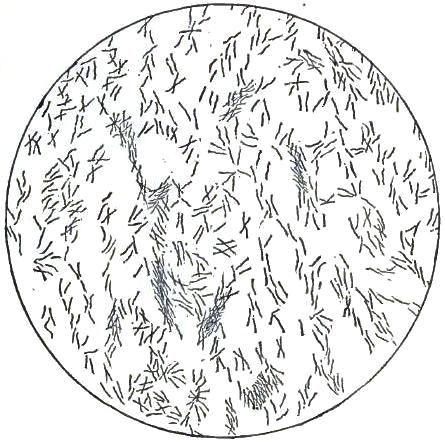

3. BACILLUS MALARIÆ

9. BACILLI FROM HUMAN SALIVA